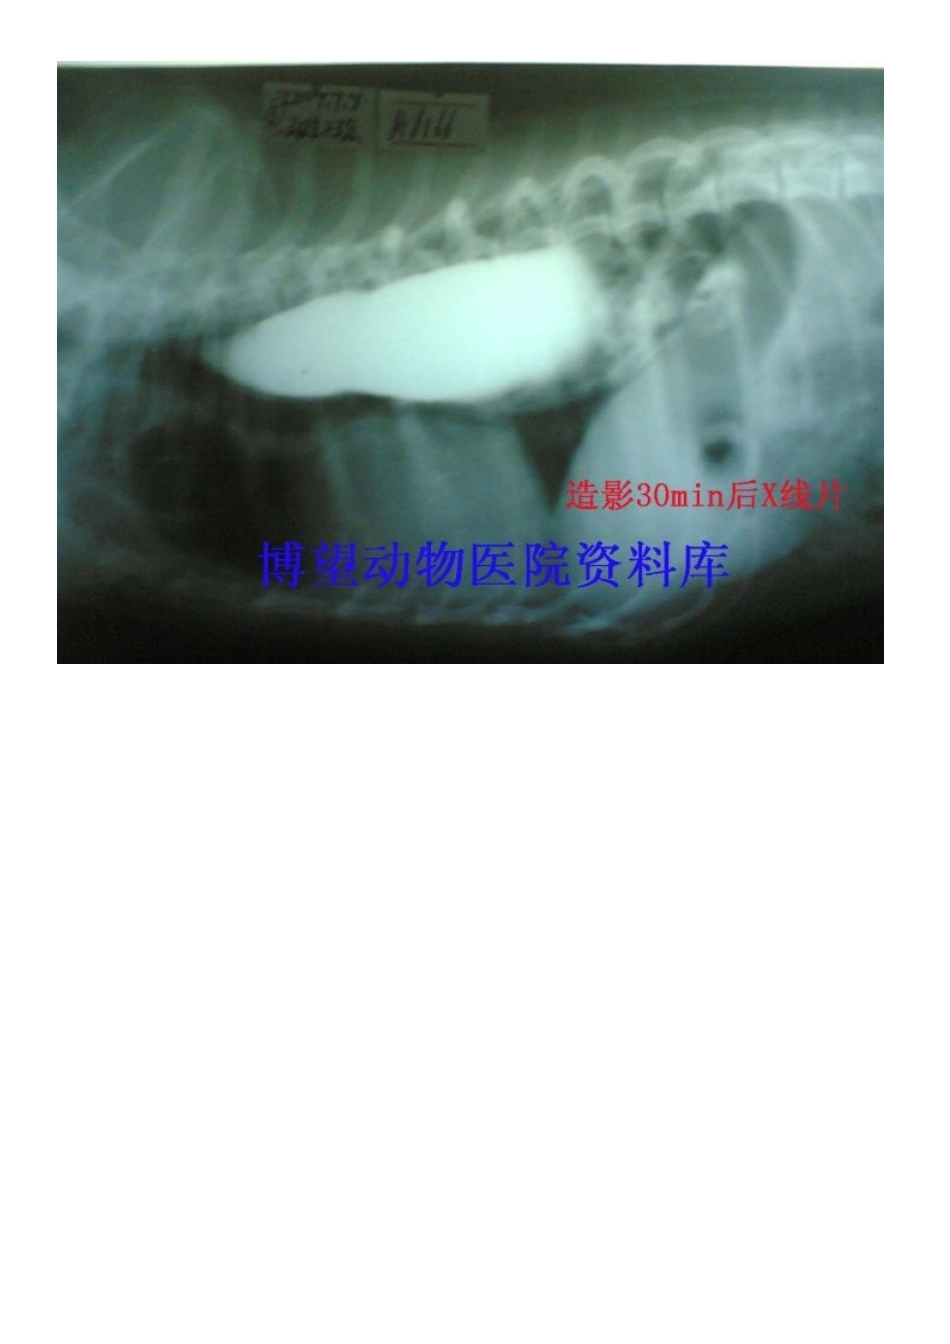

病例5——保守——成年犬巨食道症---X片VIP免费

一、定义1,成年动物发生的整食管扩张且蠕动停止.2,成年原发性巨食管症是指不明原因的食管扩张.3,成年后天性巨食管症是指原因明了的食管扩张.4,成年巨食管症在犬常引起逆流而在猫少见.二、病因1,许多病例的病因不清,从而导致先天性的类别.2,许多病理情况都能引起食管扩张或与之有关.3,后天性(继发)病因包括神经肌肉性疾病,免疫调节紊乱,激素失衡,中毒及炎症.三、临床症状1,发生食物和液体返流,但在进食后发生返流的时段有很大差异.2,吞咽痛在炎症和过度扩张时可见,表现出唾液分泌过多,反复吞咽和颈部姿势异常.3,伴随食物发酵而出现口臭.4,当发生异物性肺炎时出现呼吸紧迫(湿咳,啰音,呼吸困难).5,营养不良会导致严重的恶病质或虚弱.6,与继发病因有关的症状将可看到:A,肌肉痛和多肌炎性僵步.B,神经肌肉病性虚弱.C,中毒或阿狄森病(肾上腺皮质机能减退)引起的胃肠症状.四、诊断1,准确了解病史很重要.A,呕吐和返流混淆易产生误诊.B,成年动物,尤其是犬有返流病史者怀疑巨食管症.2,体检可能提供继发性巨食管症病因的线索.A,注意肌肉痛,虚弱,神经性缺损和精神状态的变化.B,在肾上腺皮质机能紊乱时可见到皮肤异常.3,X光照相是合适的.A,颈胸部一般放射检查即可发现食管内存留气体、液体和食物积留.B,异物性肺炎时可见肺泡浊斑.C,食管部钡餐造影可显示其扩张及其他结构异常(.D,荧光镜透视(若适宜)可获得巨食管迟缓的有用资料.4,实验室诊断很有益.A,最基本的实验室检查包括全血细胞计数,全面的生化指标检测和尿液分析.B,肌激酶分析可判断肌肉病或肌炎,而测定血清胆固醇可诊断皮质激素功能紊乱.C,所有怀疑肌无力而巨食管症不确切的病例均应作乙酰胆碱受体滴度测定.D,临床可疑病例可作传统实验室检查.5,巨食管症诊断一般无须作食管镜检查,除非怀疑有肿瘤或其他结构异常.五、治疗1,患有后天性巨食管症的动物随时都可针对引起食管扩张的因素进行治疗,多数会改善机关机能.2,先天性巨食管症及药物治疗无效的后天性巨食管症可进行对症治疗.A,抬高饲槽位置有利于食物通过而入胃.B,通常饲喂少量满足体能需要即可.C,改变食物硬度(流汁与大丸料比较)看最能耐受哪种日粮.一般固体颗粒料会更好的刺激食管蠕动收缩.D,患有严重吸入性肺炎的动物需特别注意.3,作胃造影术后以造管投喂既可保证营养供应,可减少误吸的危险.4,可广谱抗菌药治疗细菌感染.5,机能促进药效果尚未证实.A,西沙比利(促进剂)0.5mg/kg,PO,BID可改善猫的食管功能底下.B,有报道证实可能改善某些犬的巨食管症临床症状.六、监护1,每隔1~2个月复查以监测病情发展.2,复查胸片以证实食管扩张的异物性肺炎.3,成年巨食管症一般预后不良.A,原发病的动物往往死亡或因病而施行安乐死.B,获得性疾病的动物药物治疗可能有效.C,犬由于严重肌无力引起的巨食管症预后良好.用支持疗法半个疗程即可奏效.